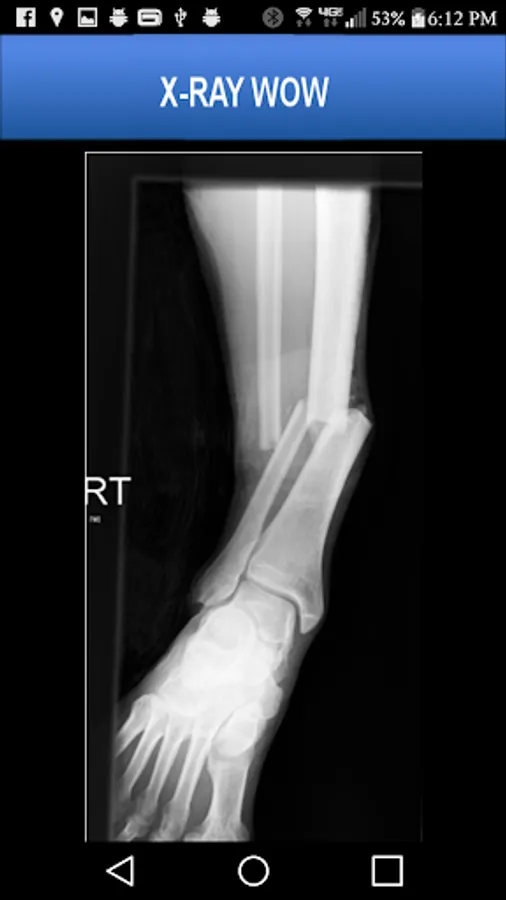

A collection of authentic x-ray images of 20 patients who have experienced serious trauma or unusual surgical procedures.

More than 55 x-ray images are included, many pointing out pathology using arrows and lines. The images may be pinch-zoomed.